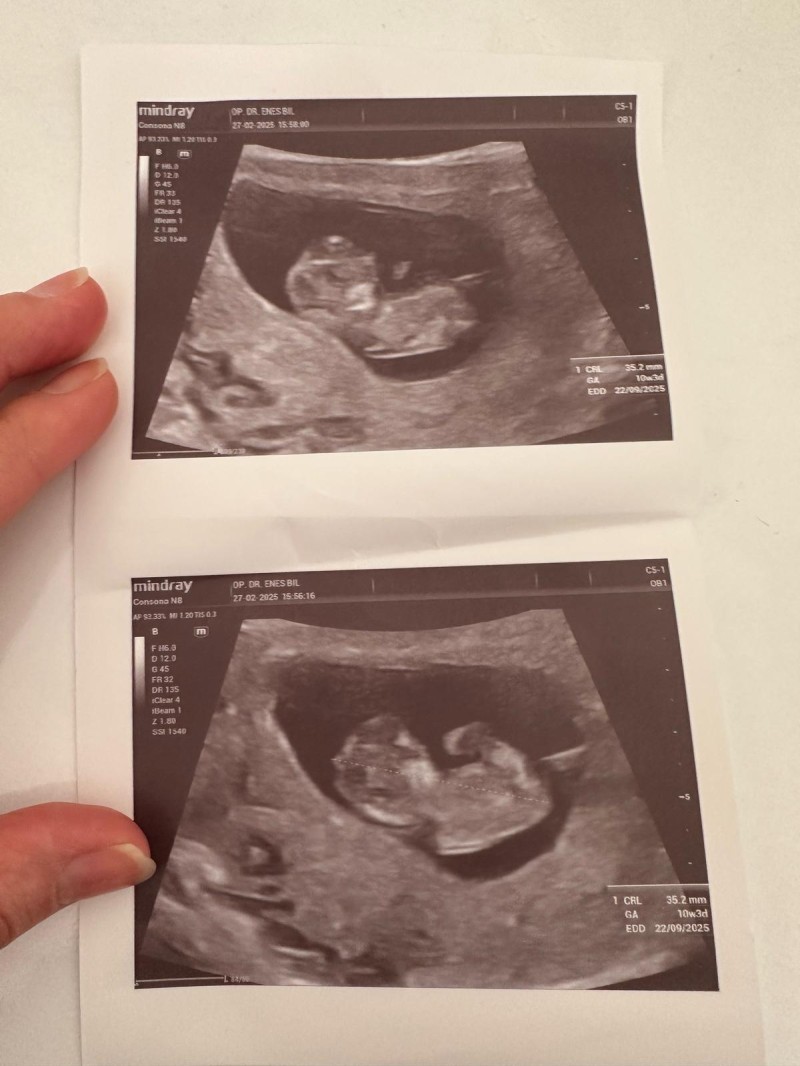

Ablam çok heyecanlı bizde ortak olmak istedik tahmin eder misiniz yada hiss icinizden ne geçiyorsa (cinsiyet)

image